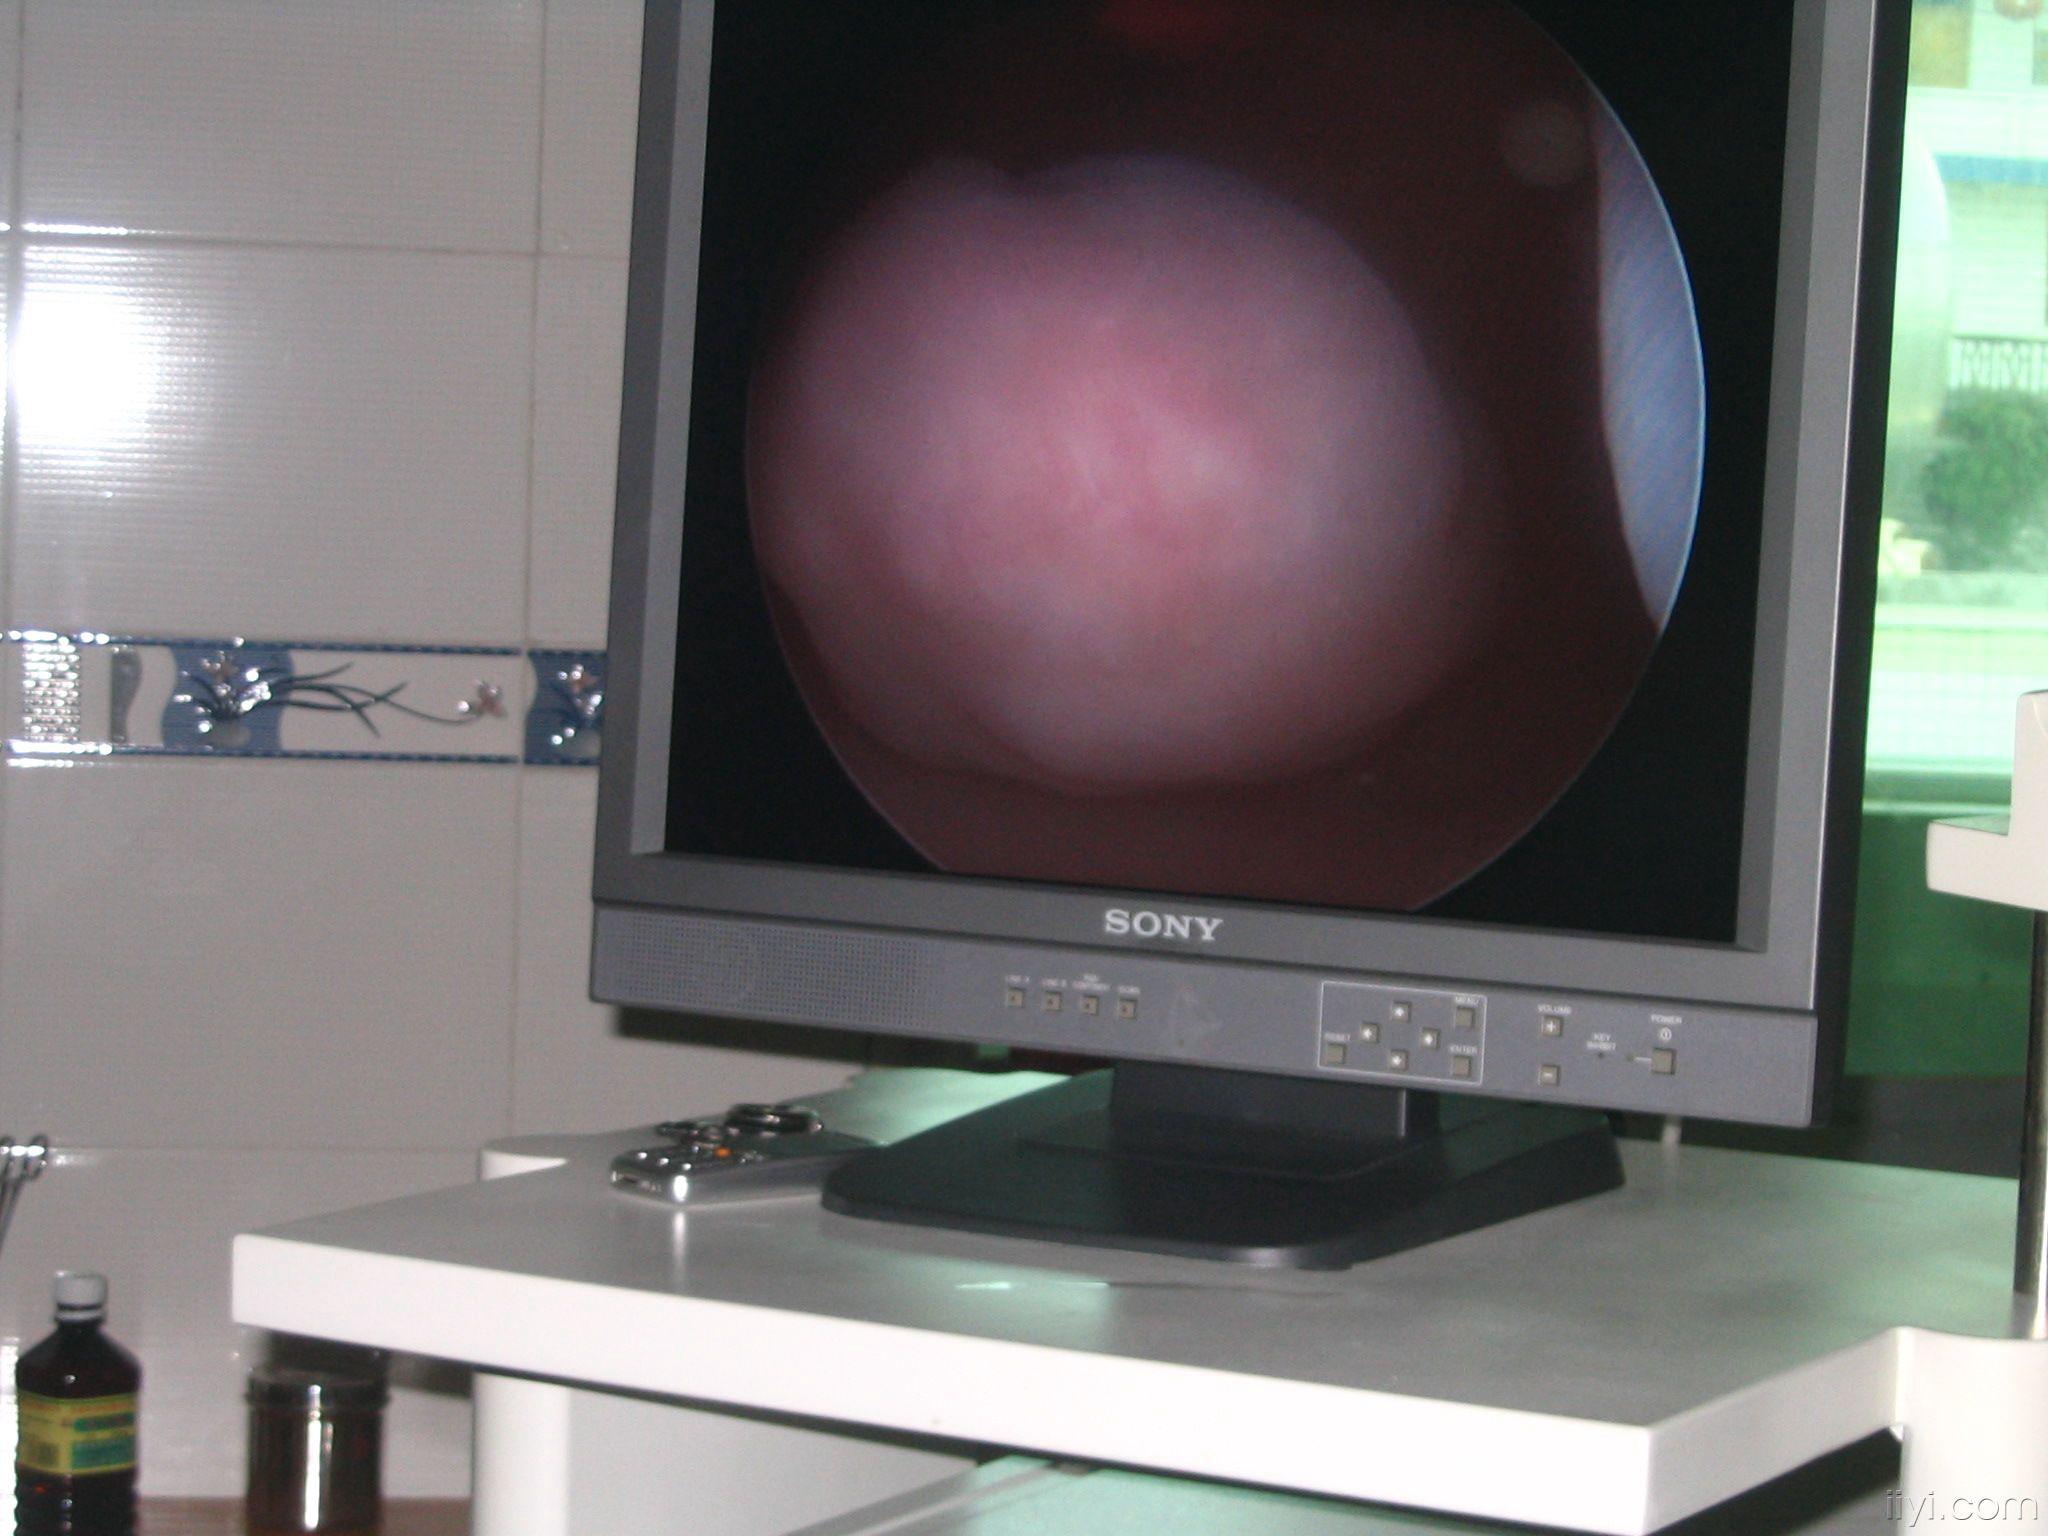

宫腔镜下子宫穿孔图片

宫腔镜下子宫穿孔图片,腹腔镜下子宫穿孔图片

[图片] 经典宫腔镜图片

宫腔镜图片

宫腔镜检查图片